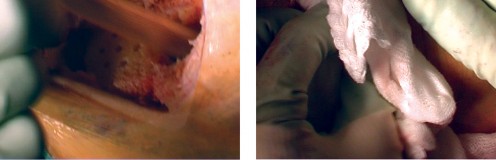

Cementing Technique and Implant Implantation

The hallmark of a cemented TKA is the creation of a durable, interlocking micro-mechanical bond between the host trabecular bone and the polymethylmethacrylate (PMMA) bone cement. PMMA is not an adhesive; it functions as a grout. Therefore, meticulous bone bed preparation is the single most critical factor in preventing aseptic loosening. The resected bony surfaces must be aggressively cleansed using pulsatile lavage to remove marrow, fat, and debris, exposing the porous cancellous bone. Sclerotic areas should be perforated with a small drill bit to enhance cement interdigitation.

The bone must be thoroughly dried immediately prior to cement application. High-viscosity cement is typically mixed under a vacuum to reduce porosity and increase fatigue strength. The cement is applied during its "doughy" phase to both the implant surfaces and the prepared bone. The components are then impacted into place.

Crucially, the cement must be pressurized into the cancellous bone to achieve a penetration depth of 3 to 4 mm. Once the components are seated, all extruded peripheral cement must be meticulously removed with a curette, particularly from the posterior aspect of the condyles and the posterolateral corner, where retained cement fragments can cause severe postoperative pain, third-body wear, or impingement. The knee is then held in full extension with axial compression applied until the exothermic polymerization process is complete and the cement is fully cured.